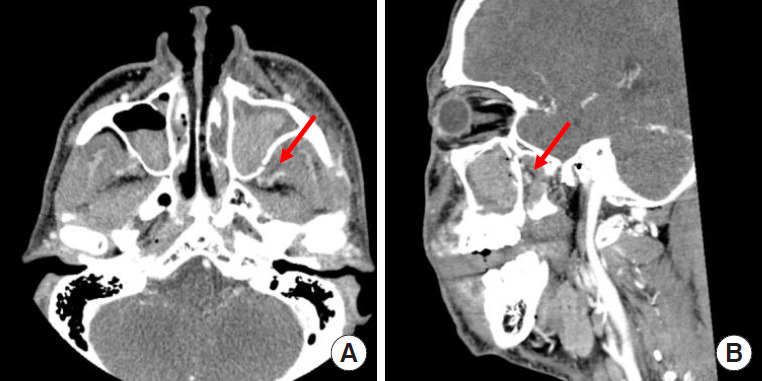

Fig. 2.

Contrast-enhanced computed tomography images show the location of the pseudoaneurysm in the branches of the left internal maxillary artery with sinus hemorrhage (red arrow). (A) Axial image. (B) Sagittal image.